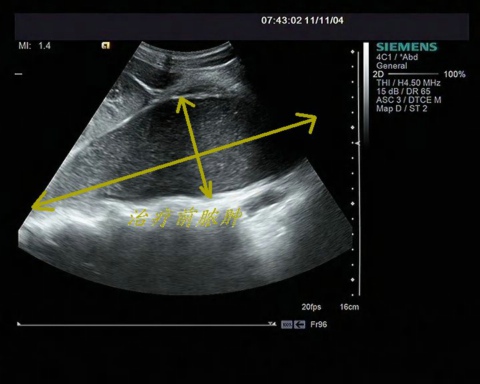

住院后,做了各项相关检查,双侧腰大肌巨大脓肿的病因还是不明,经过全科医生讨论一致认为目前患者病情不适于手术治疗。在这种特殊情况下请求医学影像超声科蔡艳主任会诊。记得初次做超声检查时,患者不能平卧,采取被动体位跪着做检查的。超声提示双侧腰大肌分别可见一巨大脓肿,大小分别为20cm×10cm×10cm,15×8cm×8cm,建议患者到我科进行经超声引导下穿刺抽液冲洗置管引流术。在蔡艳主任的亲自指导及操作下,经超声引导,在患者背后分别相应的打了两个直径3mm的孔,将8.5F引流管置入脓腔引流,以及药物冲洗。在患者住院期间,共引流出草绿色的脓液约2000ml。术后第一天,周叔就可以卧床作息了,再也不用趴在床沿上熬夜啦。介入手术之前周叔由于腹肌紧张,疼痛加剧,都不能伸直腰,甚至不能平卧,生活质量很差。